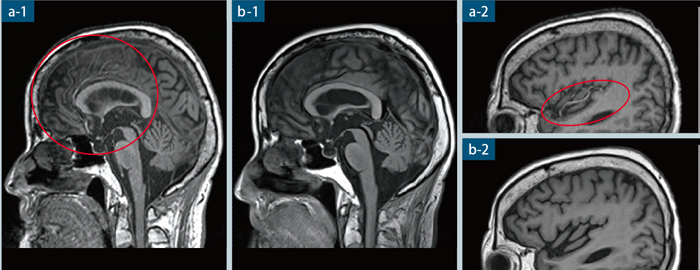

専用 脳MRI 3 高性能MRI(1.5テスラ)|施設・設備|おおたけ脳神経・漢方内科の詳細情報

高性能MRI(1.5テスラ)|施設・設備|おおたけ脳神経・漢方内科。今回導入された3T-MRIについて|名古屋セントラル病院。1.5T MAGNETOM ESSENZA 頭頸部領域における質の高い診断と検査。